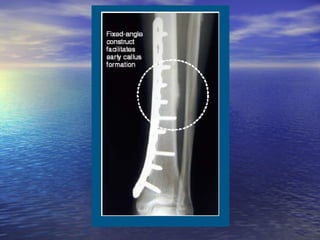

Bridge/Locked Plating Using

Locking Screws

• Screws lock to the plate, forming a

fixed-angle construct.

• Bone healing is achieved indirectly

by callus formation when using

locking screws exclusively.